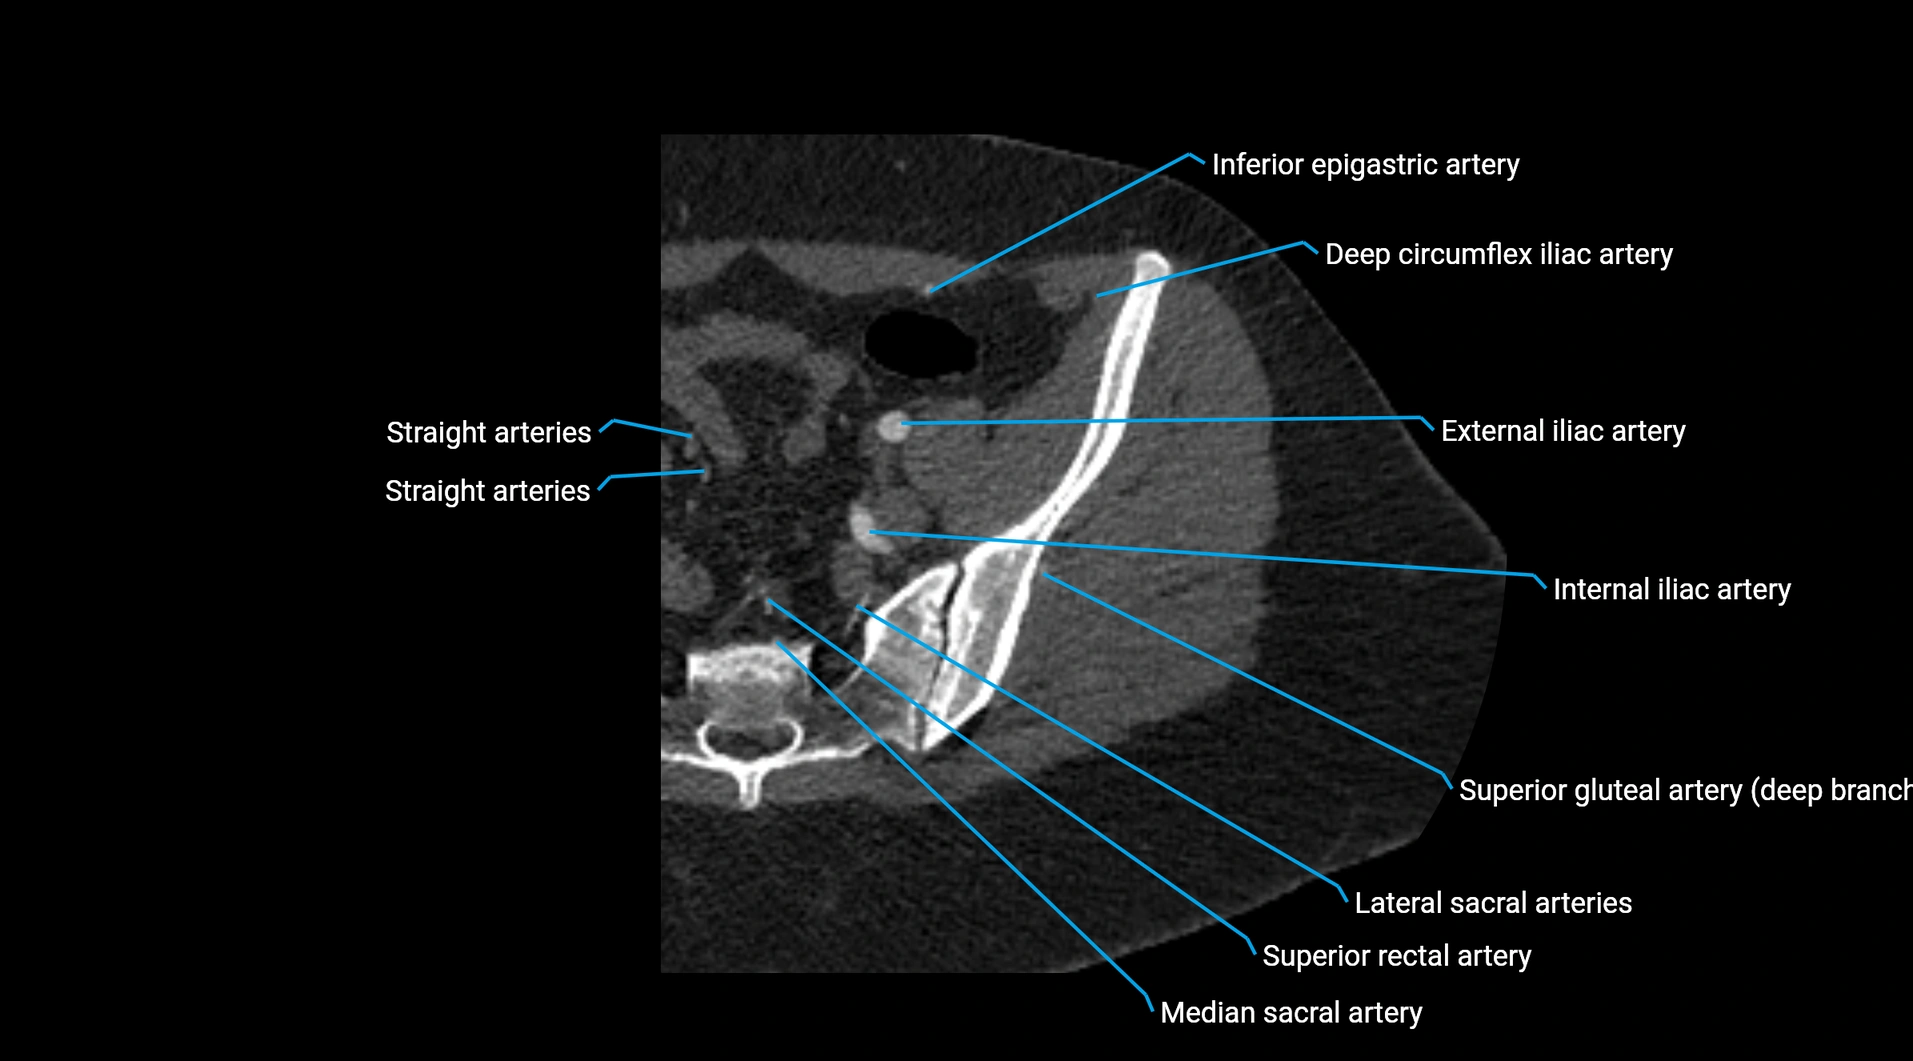

CT images

image

Contrast-enhanced CT (CTA):

• Gold standard for abdominal aortic imaging

• Provides excellent detail of lumen, wall, aneurysm, thrombus, and branch vessels

• Multiplanar and 3D reconstructions help in aneurysm measurement, stent graft planning, and dissection evaluation